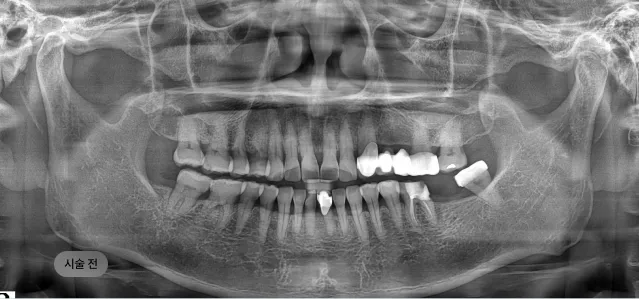

화면을 드래그하여 전/후를 비교해 보세요